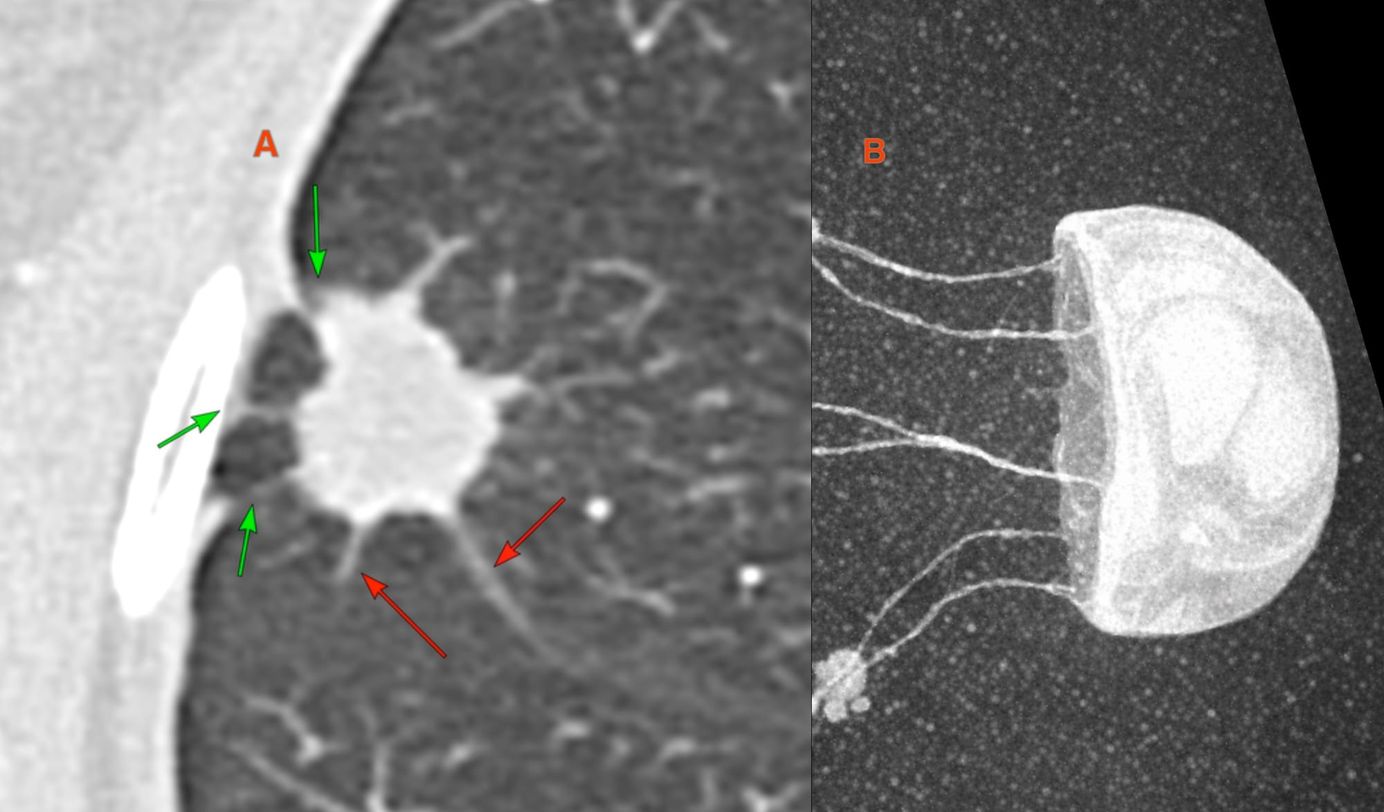

The PDIF sign is basically the presence of a fibrosing ILD typically compacted within the last 2 cm of the peridiaphragmatic lung and may suggest not just CTD-ILD but specifically myositis ILD